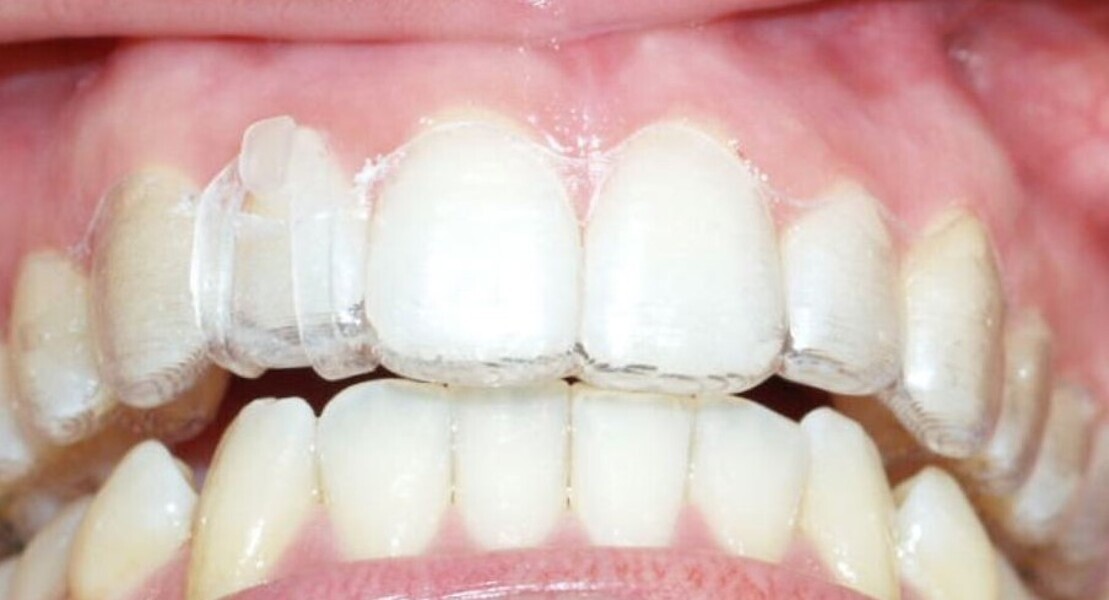

Transverse corrections

Aligners alone will fail with significant width corrections because they simply cannot accurately produce the bodily movement, bone remodelling and root torque that is required to profoundly and fully provide transverse corrections. Instead use a fixed expander. This most often involves using clear aligners only in the mandible at first while the expander of choice is widening the maxillary arch. In the time it takes the expander to be effective (four to six months), the mandibular arch movements have often been achieved with clear aligners. The case is then finished with full maxillary and mandibular aligners (Figs. 13–15). The outcome is much more assured width change while the opposing arch is being aligned.